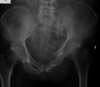

Masculino, 12 anos

Síndrome da sincondrose isquiopúbica assimétrica (Doença de Van Neck-Odelberg)

Variante da normalidade (em geral assintomático)

Crianças

Alargamento e radioluscência na sincondrose isquiopúbica, que simula neoplasias, infecção;